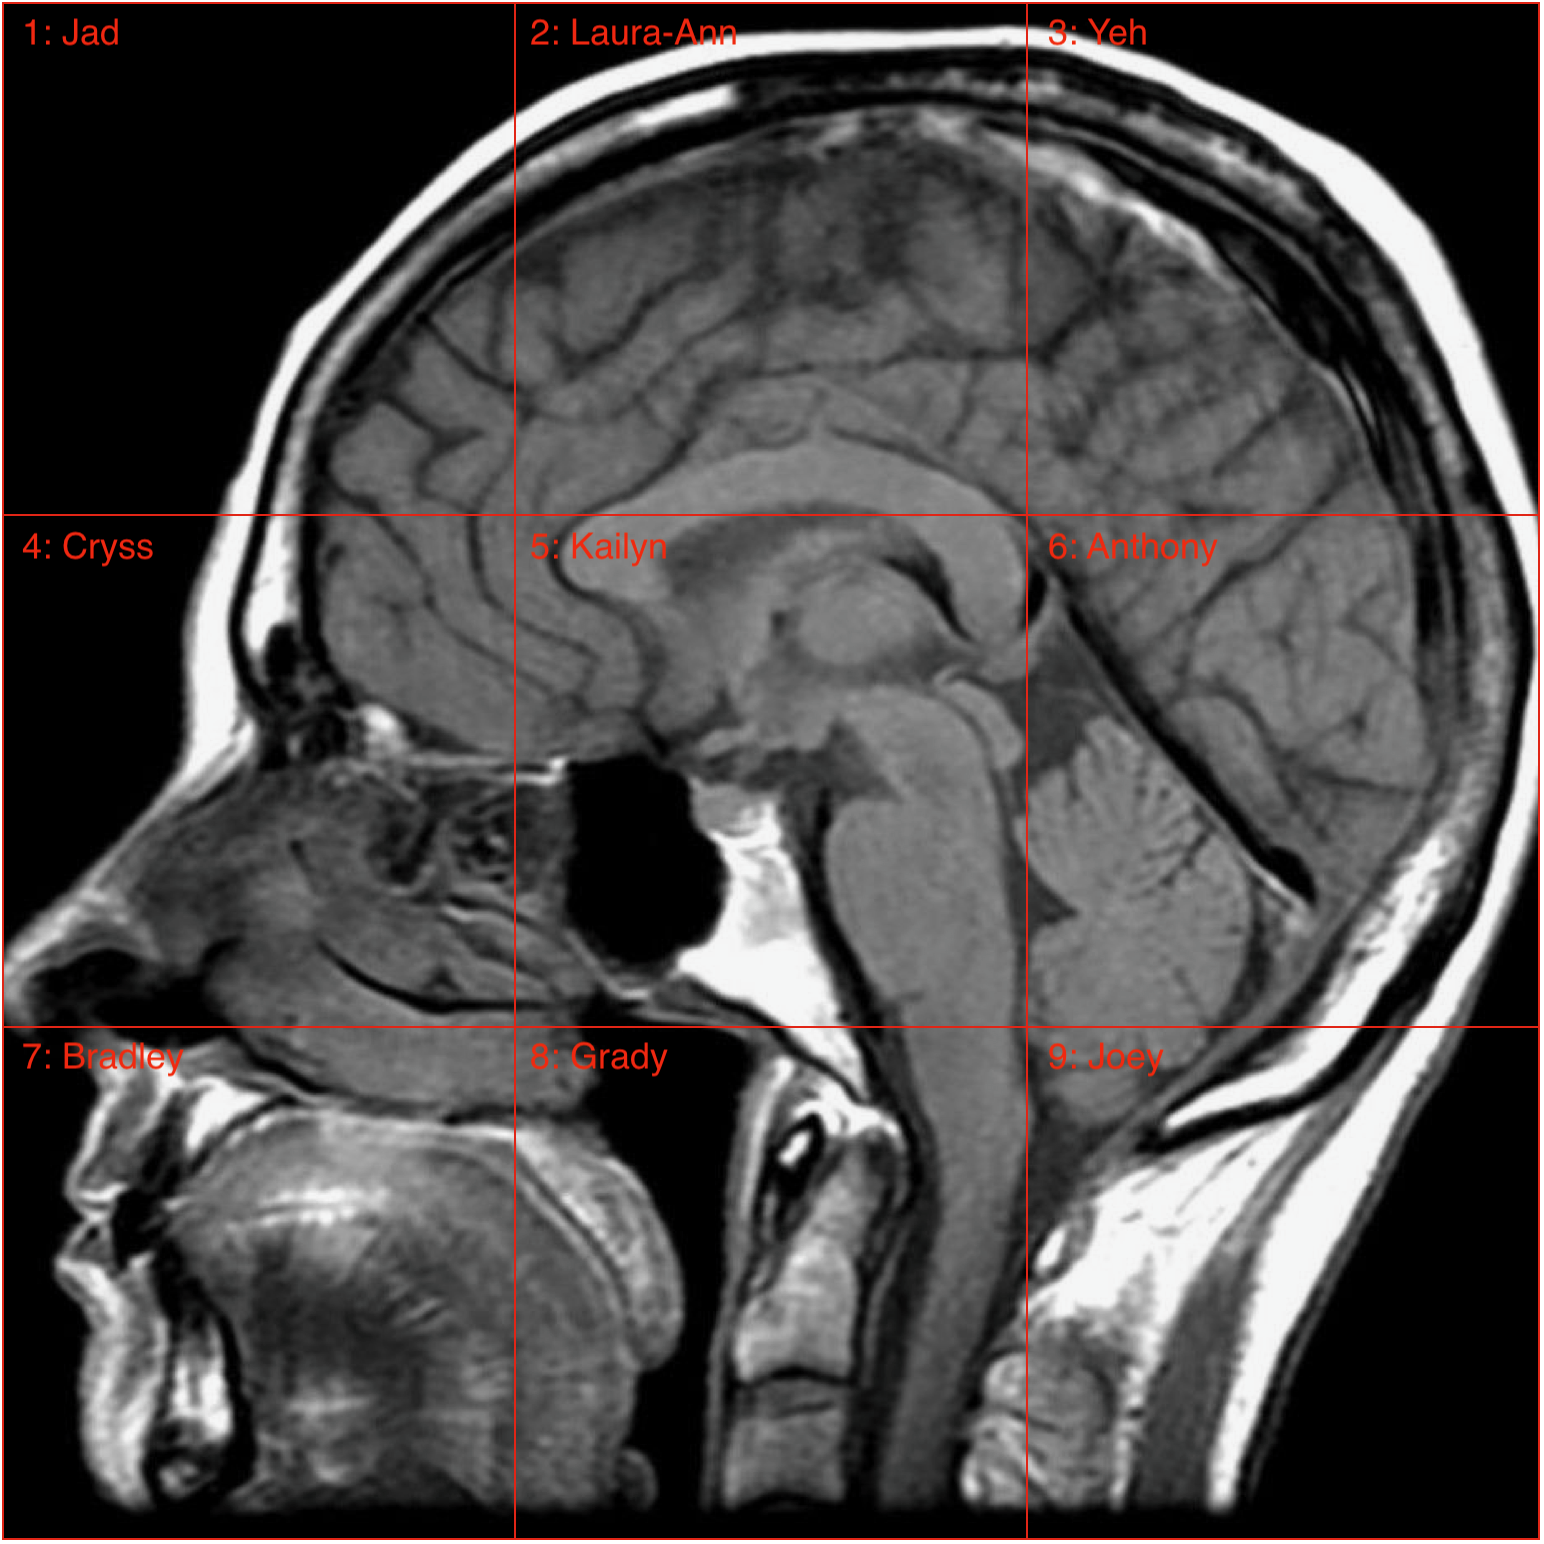

Nov 20, Friday night 7:00-9:30pm (from the homes of students around the nation!). Cryss Padilla, M.A. (BL2 Science Manager), and Dr. Bradley White (BL2 Neuroimaging Scientist), and I (Laura-Ann Petitto) noticed that our BL2 students were experiencing a touch of the Covid-19 lockdown blues. Add, as brain science students, we had a learning outcome goal whereby the students were to learn structural brain neuroanatomy and functions. So, Bradley thought to build "care packages" for each of the students, which contained a variety of goodies, including paint, paint brushes, canvases, candies, etc. (Petitto was thrilled to find Nespresso Coffee in hers!) Cryss Padilla was amazing and organized all the students to show up for a “BL2 Social Bonding Night” with a "Brain Challenge." Here, students were shown a brain divided into sections, whereupon each different section had a student’s name (see photos). Students drew their brain sections ("creative license" welcomed!). After this, Bradley is going to put all of the painted canvases together and build a grand brain mosaic to hang in BL2. PRESIDENT CORDANO: Petitto had been chatting with President Cordano about the boxes several weeks ago and thought to send her one. Why? Because she actually inspired Bradley and Cryss to think of the care packages in the first place, as she sent all 2020 graduates care packages this year due to their virtual graduation. Much to our joy, President Cordano surprised us all and actually showed up for the event and stayed for more than an hour!!! The students were utterly thrilled - made them feel special and the event indeed lifted all of our spirits.